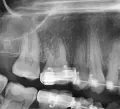

Сомневаюсь в профессионализме доктора, который Вас смотрел. Так как для постановки диагноза перелом корня, прицельного снимка как у Вас, тем более плёночного недостаточно.

Вам необходимо сделать 3D снимок Вашего зуба и обратиться к специалисту более высокого класса.